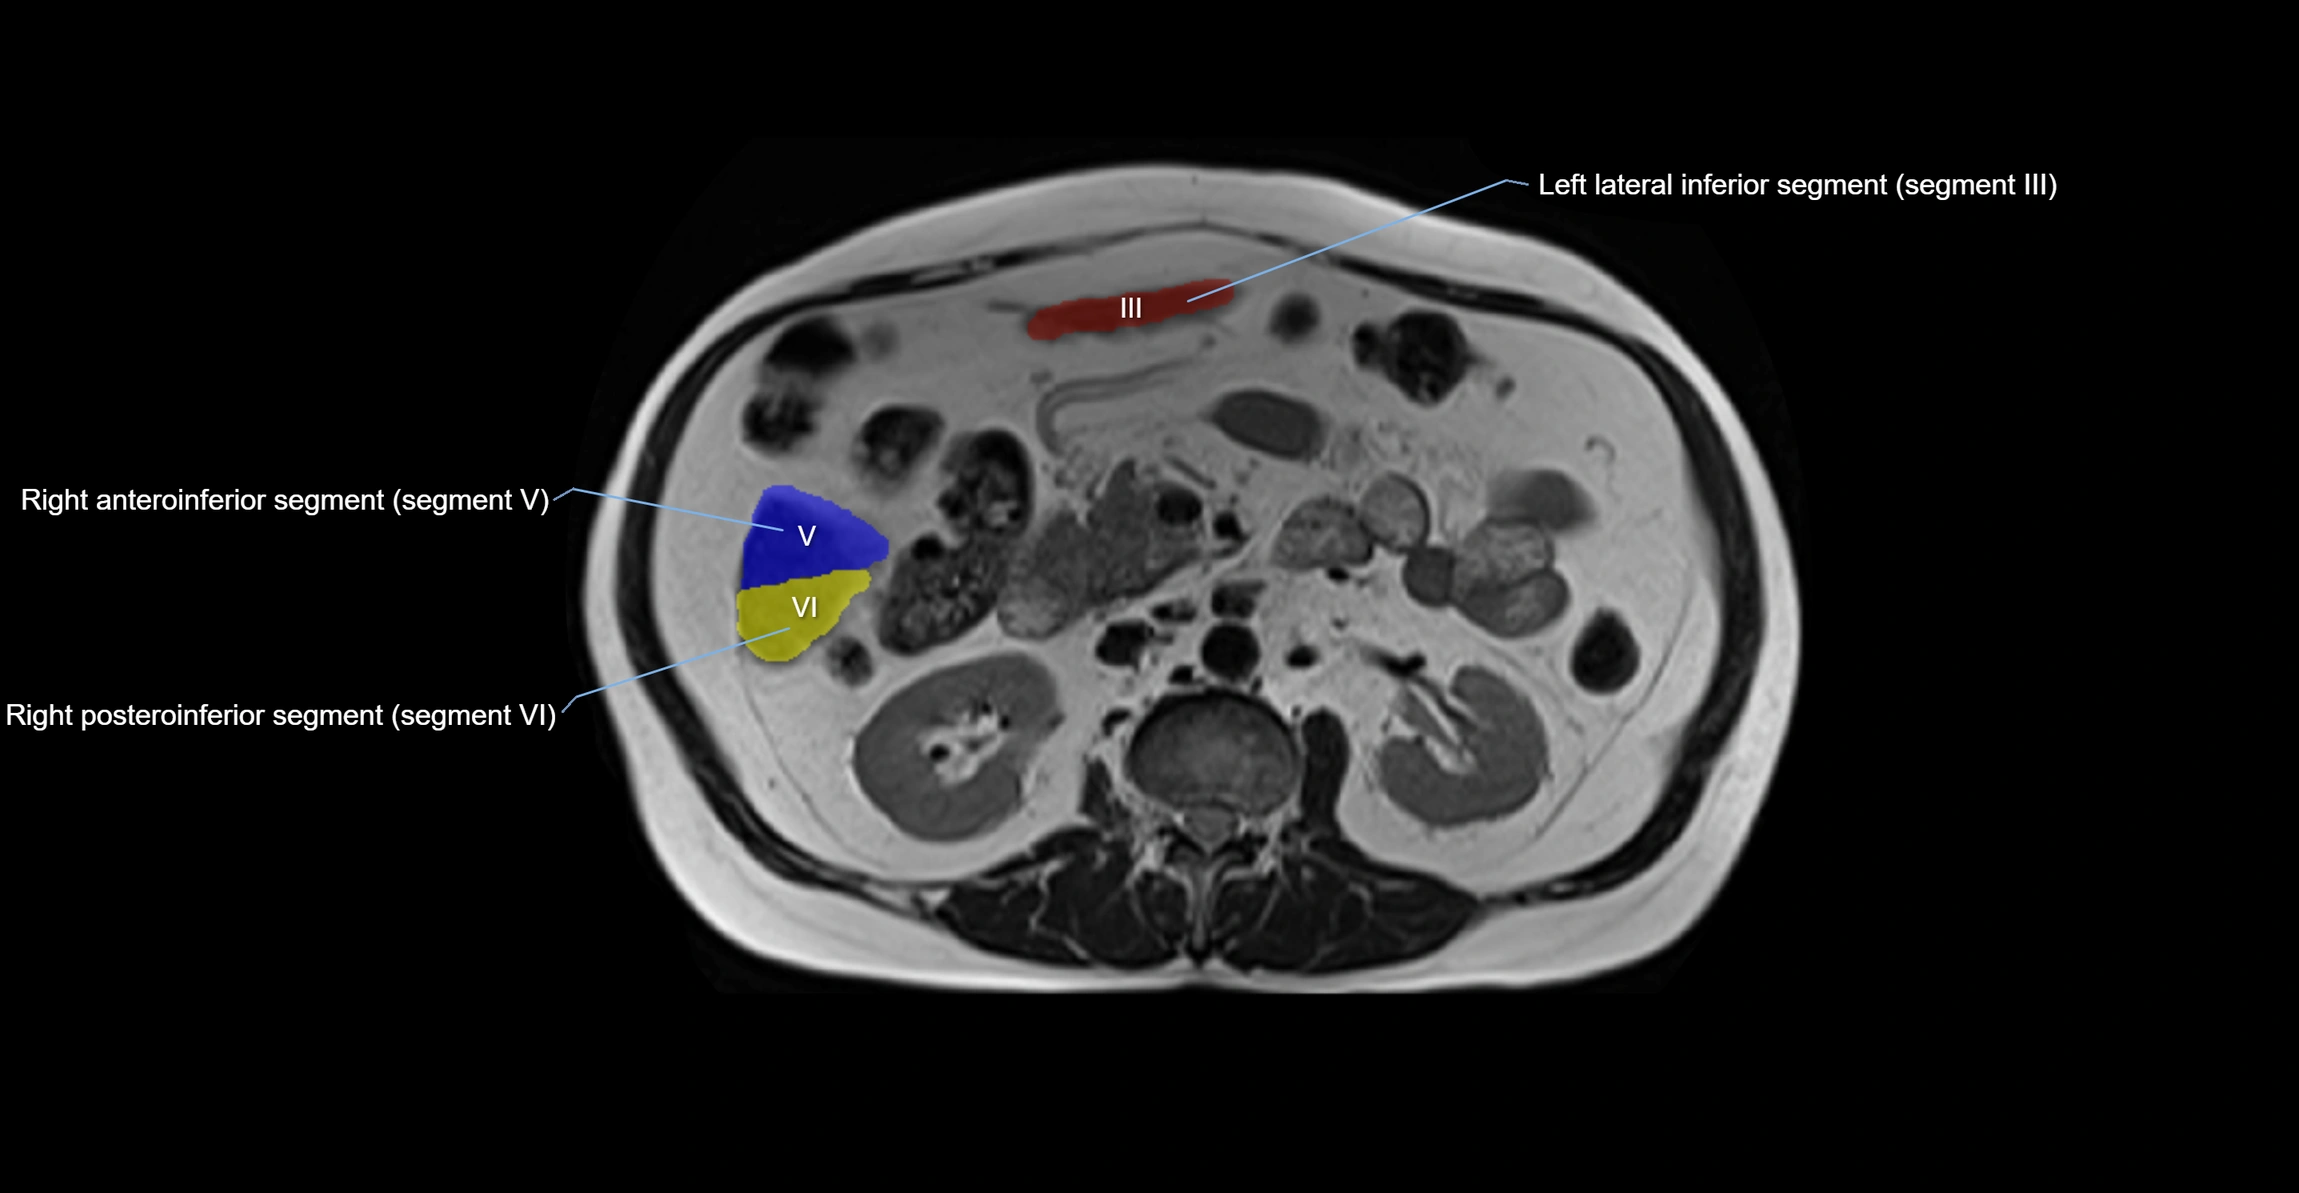

The caudate lobe of the liver is a distinct anatomical subdivision of the liver, designated as segment I in Couinaud’s classification. It lies on the posterior surface of the liver, between the fissure for the ligamentum venosum (left boundary) and the groove for the inferior vena cava (IVC) (right boundary). Superiorly, it is related to the posterior liver surface, and inferiorly it is separated from the left lobe by the porta hepatis.

The caudate lobe is unique because it receives dual portal venous and arterial inflow from both the right and left portal veins and hepatic arteries. It also has independent venous drainage directly into the IVC via multiple small hepatic veins, unlike other lobes that drain through the three main hepatic veins.

This anatomical autonomy makes the caudate lobe especially significant in liver surgery, transplantation, and hepatic venous outflow obstruction syndromes (e.g., Budd–Chiari syndrome). Enlargement of the caudate lobe is a characteristic imaging feature in chronic liver disease and cirrhosis.